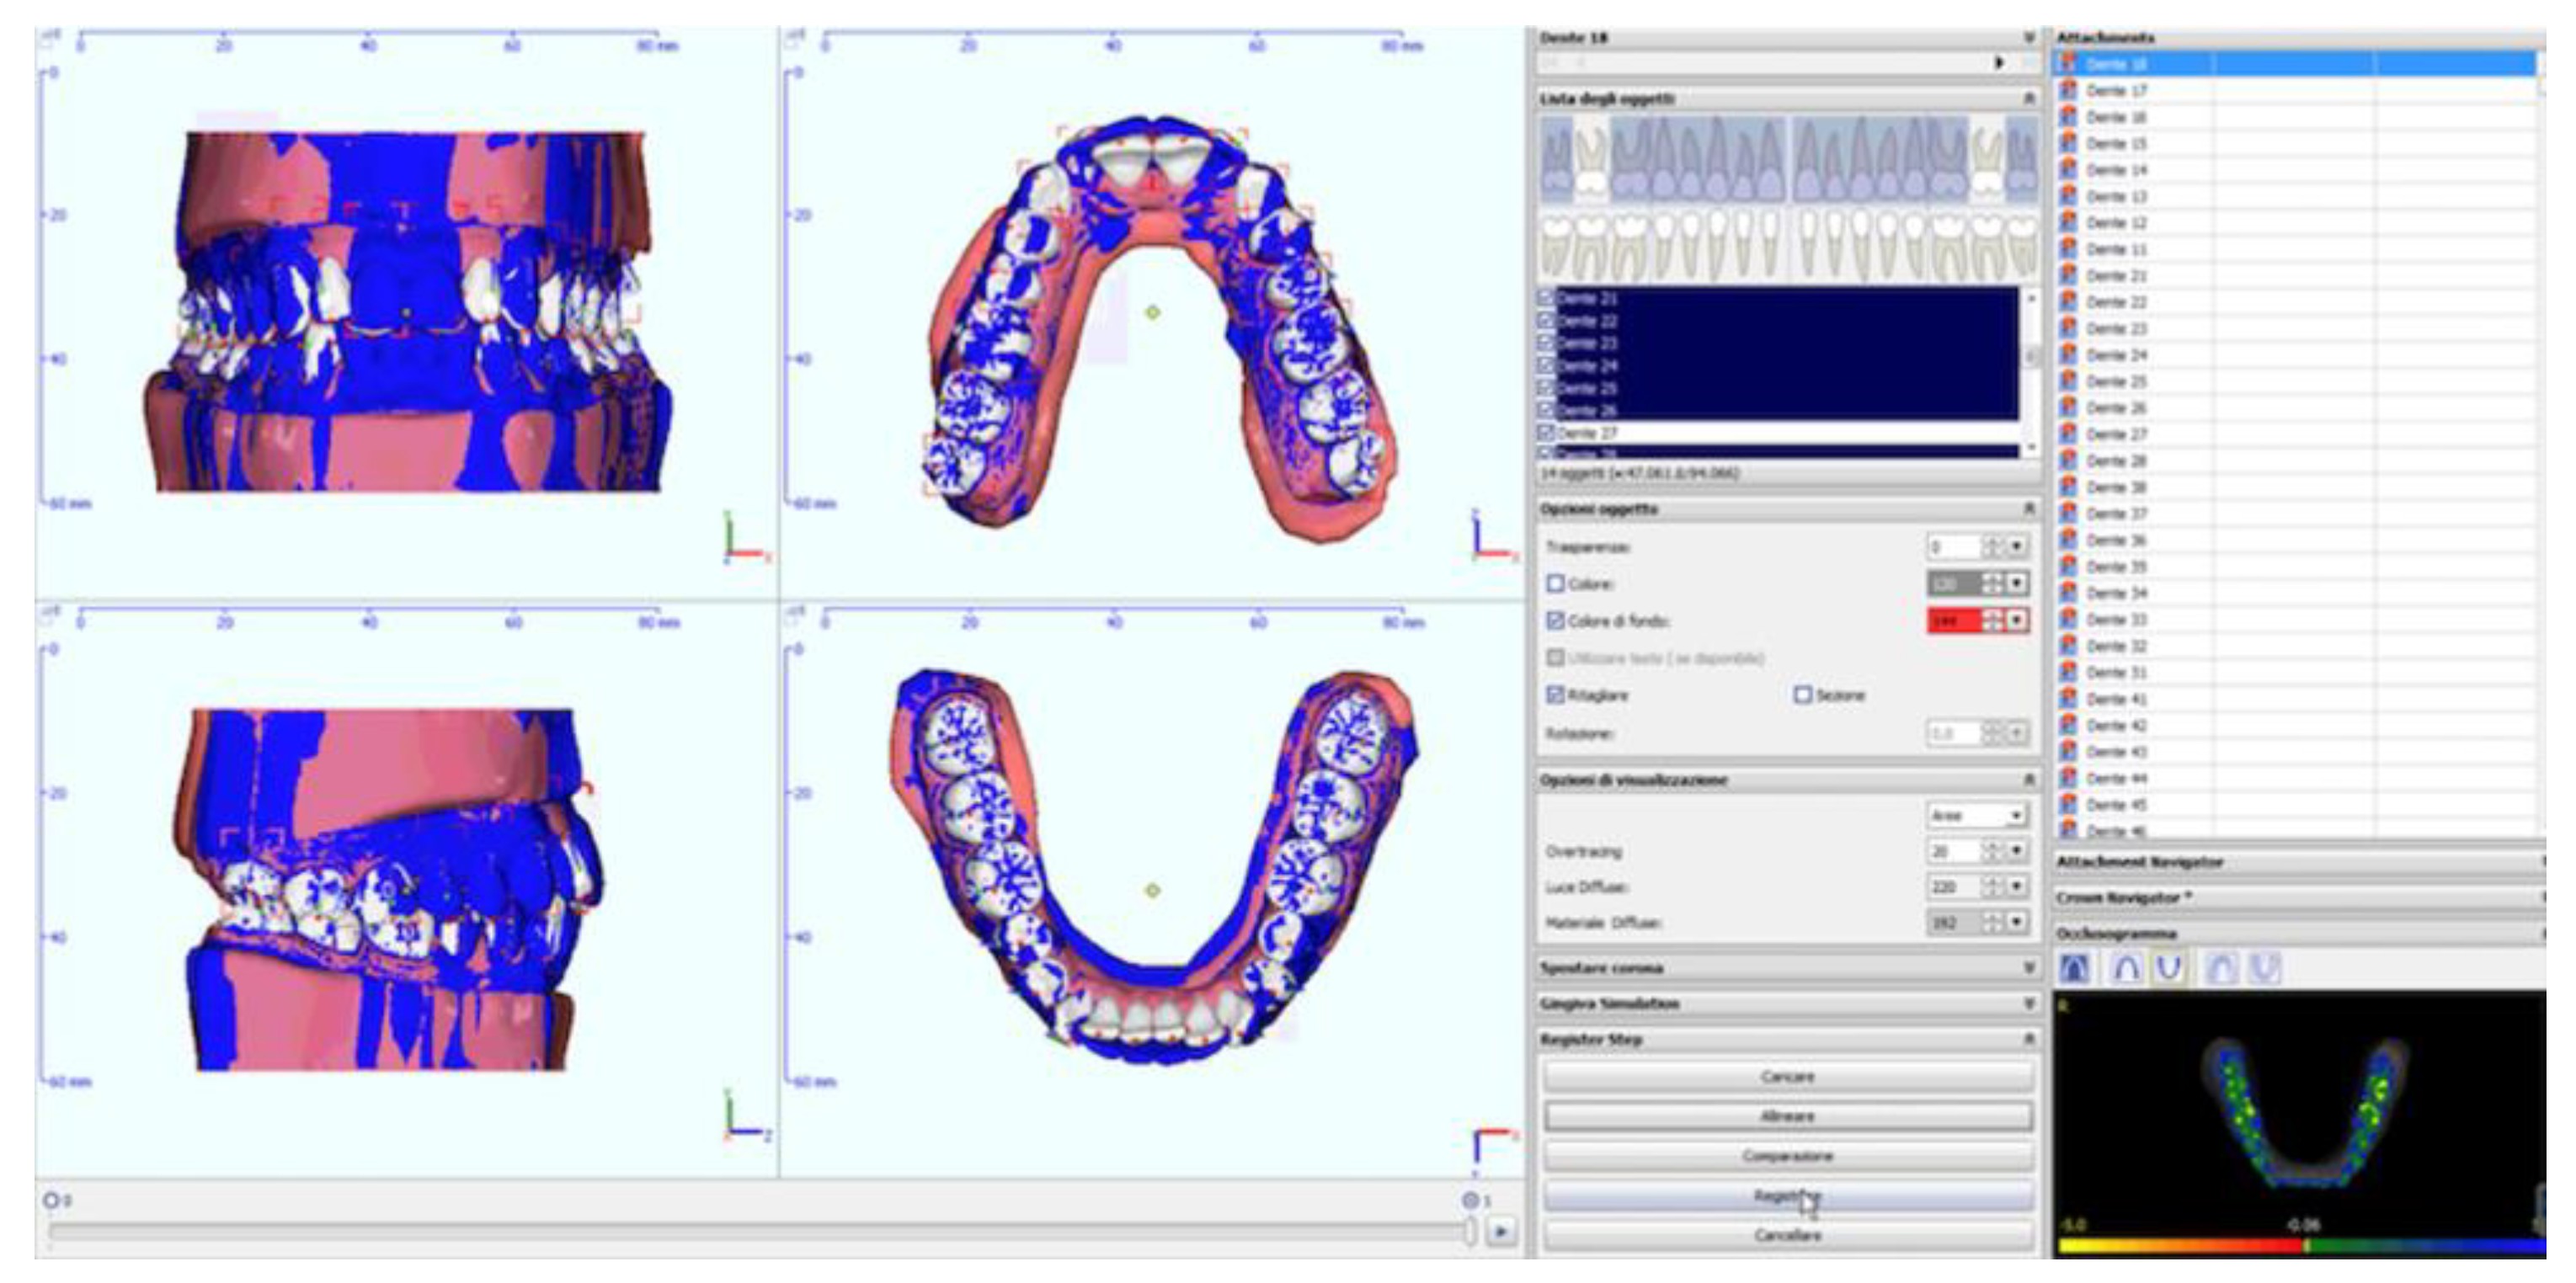

2.2. Analysis of Digital Models

- Prescribed movements (T1): the difference between the pre-treatment and reference model;

- Achieved movements (T2): the difference between the pre-treatment and pre-finishing model (Figure 3) for each movement investigated (inclination, angulation and rotation) and for each tooth (where present, third molars were excluded).